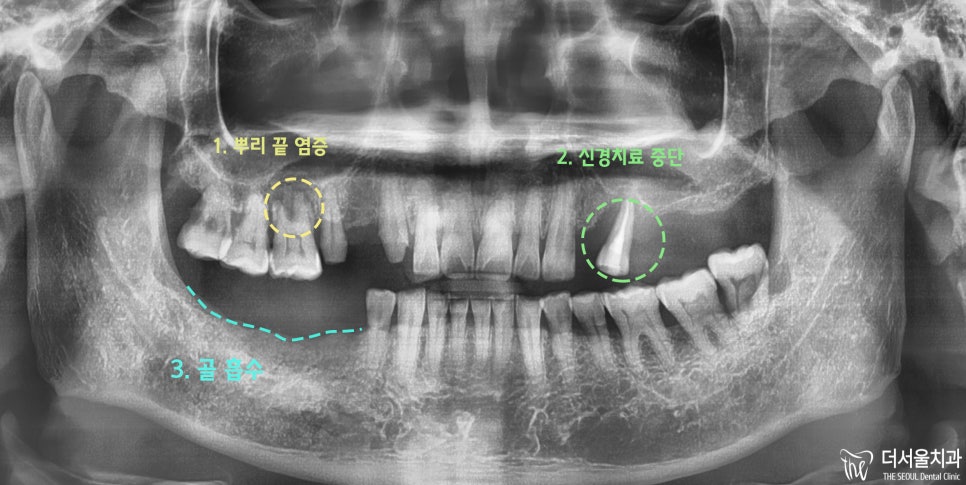

파노라마 촬영 결과

아래와 같은 사실을 알 수 있었습니다.

#16번: 심한 뿌리 끝 염증

#25번: 신경치료 중단 및 골 파괴

#40번대: 치아 상실에 따른 골 흡수

이러한 문제점을 해결하기 위해

발치 및 임플란트를 계획을 수립하게 되었습니다.